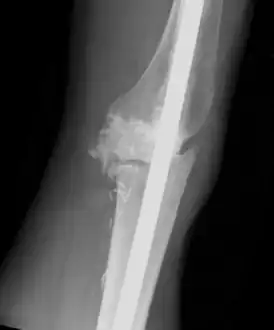

Individual with tumoral calcinosis- Lateral radiograph of the left knee demonstrating an intramedullary rod

Oblique radiograph of the right hand demonstrating soft tissue calcification, characteristic of dialysis related metastatic calcification.